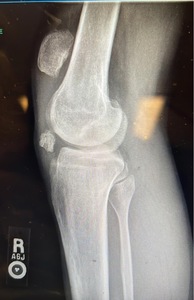

Decision was made to proceed with range of motion of the knee 0-30 degrees and progress 15° every 2 weeks. A range-of-motion brace was applied. The patient was asked to do quadriceps isometric exercises and to weight bear partially using crutches. At 10 weeks post op, knee ROM was 0-45° and repeat Xray showed stable patellar repair (Figure 4). Patient was fully weight bearing independently. He continued physical therapy for a total of 5 months. At 24 weeks, pain was rated as a 1/10 only and the patient was given clearance to resume work. Last follow up was at 32 weeks post op. The patient had completed physical therapy and was back to work. His pain improved and was rated as a 1-2/10 depending on the workload subjected to his knee. ROM was 0-75 of flexion.